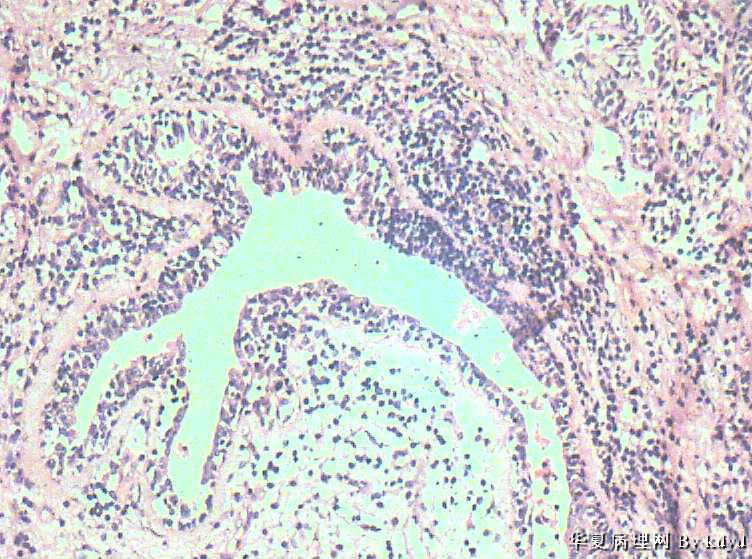

B3997左乳肿瘤--浸润性导管癌?

37岁,女。左侧乳腺肿块发现5个多月,伴隐痛。

手术见:肿块与周围组织分界不清,无明显包膜。

大体:不整形组织大小约3.5*35*2CM,未见明显包膜。质较软,切面浅黄色,一侧见一小囊腔直径约0.8CM囊壁较粗糙。

标签:乳腺浸润性导管癌 原位癌

浸润性乳腺导管癌?

乳腺浸润性导管癌

应该是个浸润性导管癌

但是,片子质量欠佳

不太敢直接下

诊断乳腺浸润性导管癌确实有些担心,制片质量确实要提高,制作优良的切片,是正确诊断的前提。

囊壁内大量炎细胞浸润,囊壁被覆细胞有明显异型,可见核分裂,考虑癌,不知有无陷阱